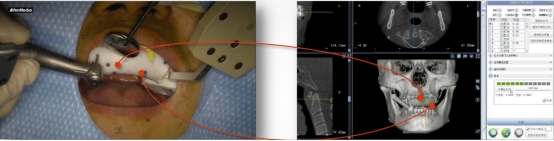

成功率高:术前口内模拟种植,避开神经血管,设计种植方案,运用计算机三维重建与可视化技术,清晰展现患者口内结构,保证了复杂病例的成功率。

实时引导:全程监控手术工具与解剖结构的位置关系,轻松把控种植位点、角度和深度,实时引导术者按计划进行种植。

数字化动态导航系统犹如口腔中的GPS导航”,简单来说就是通过虚拟数字化软件设计,提前设计好修复体三维位置,结合精准的红外光学定位技术,在种植手术过程中,实现全程实时的导航。使使种植医生实时监控和调整手术的进程。